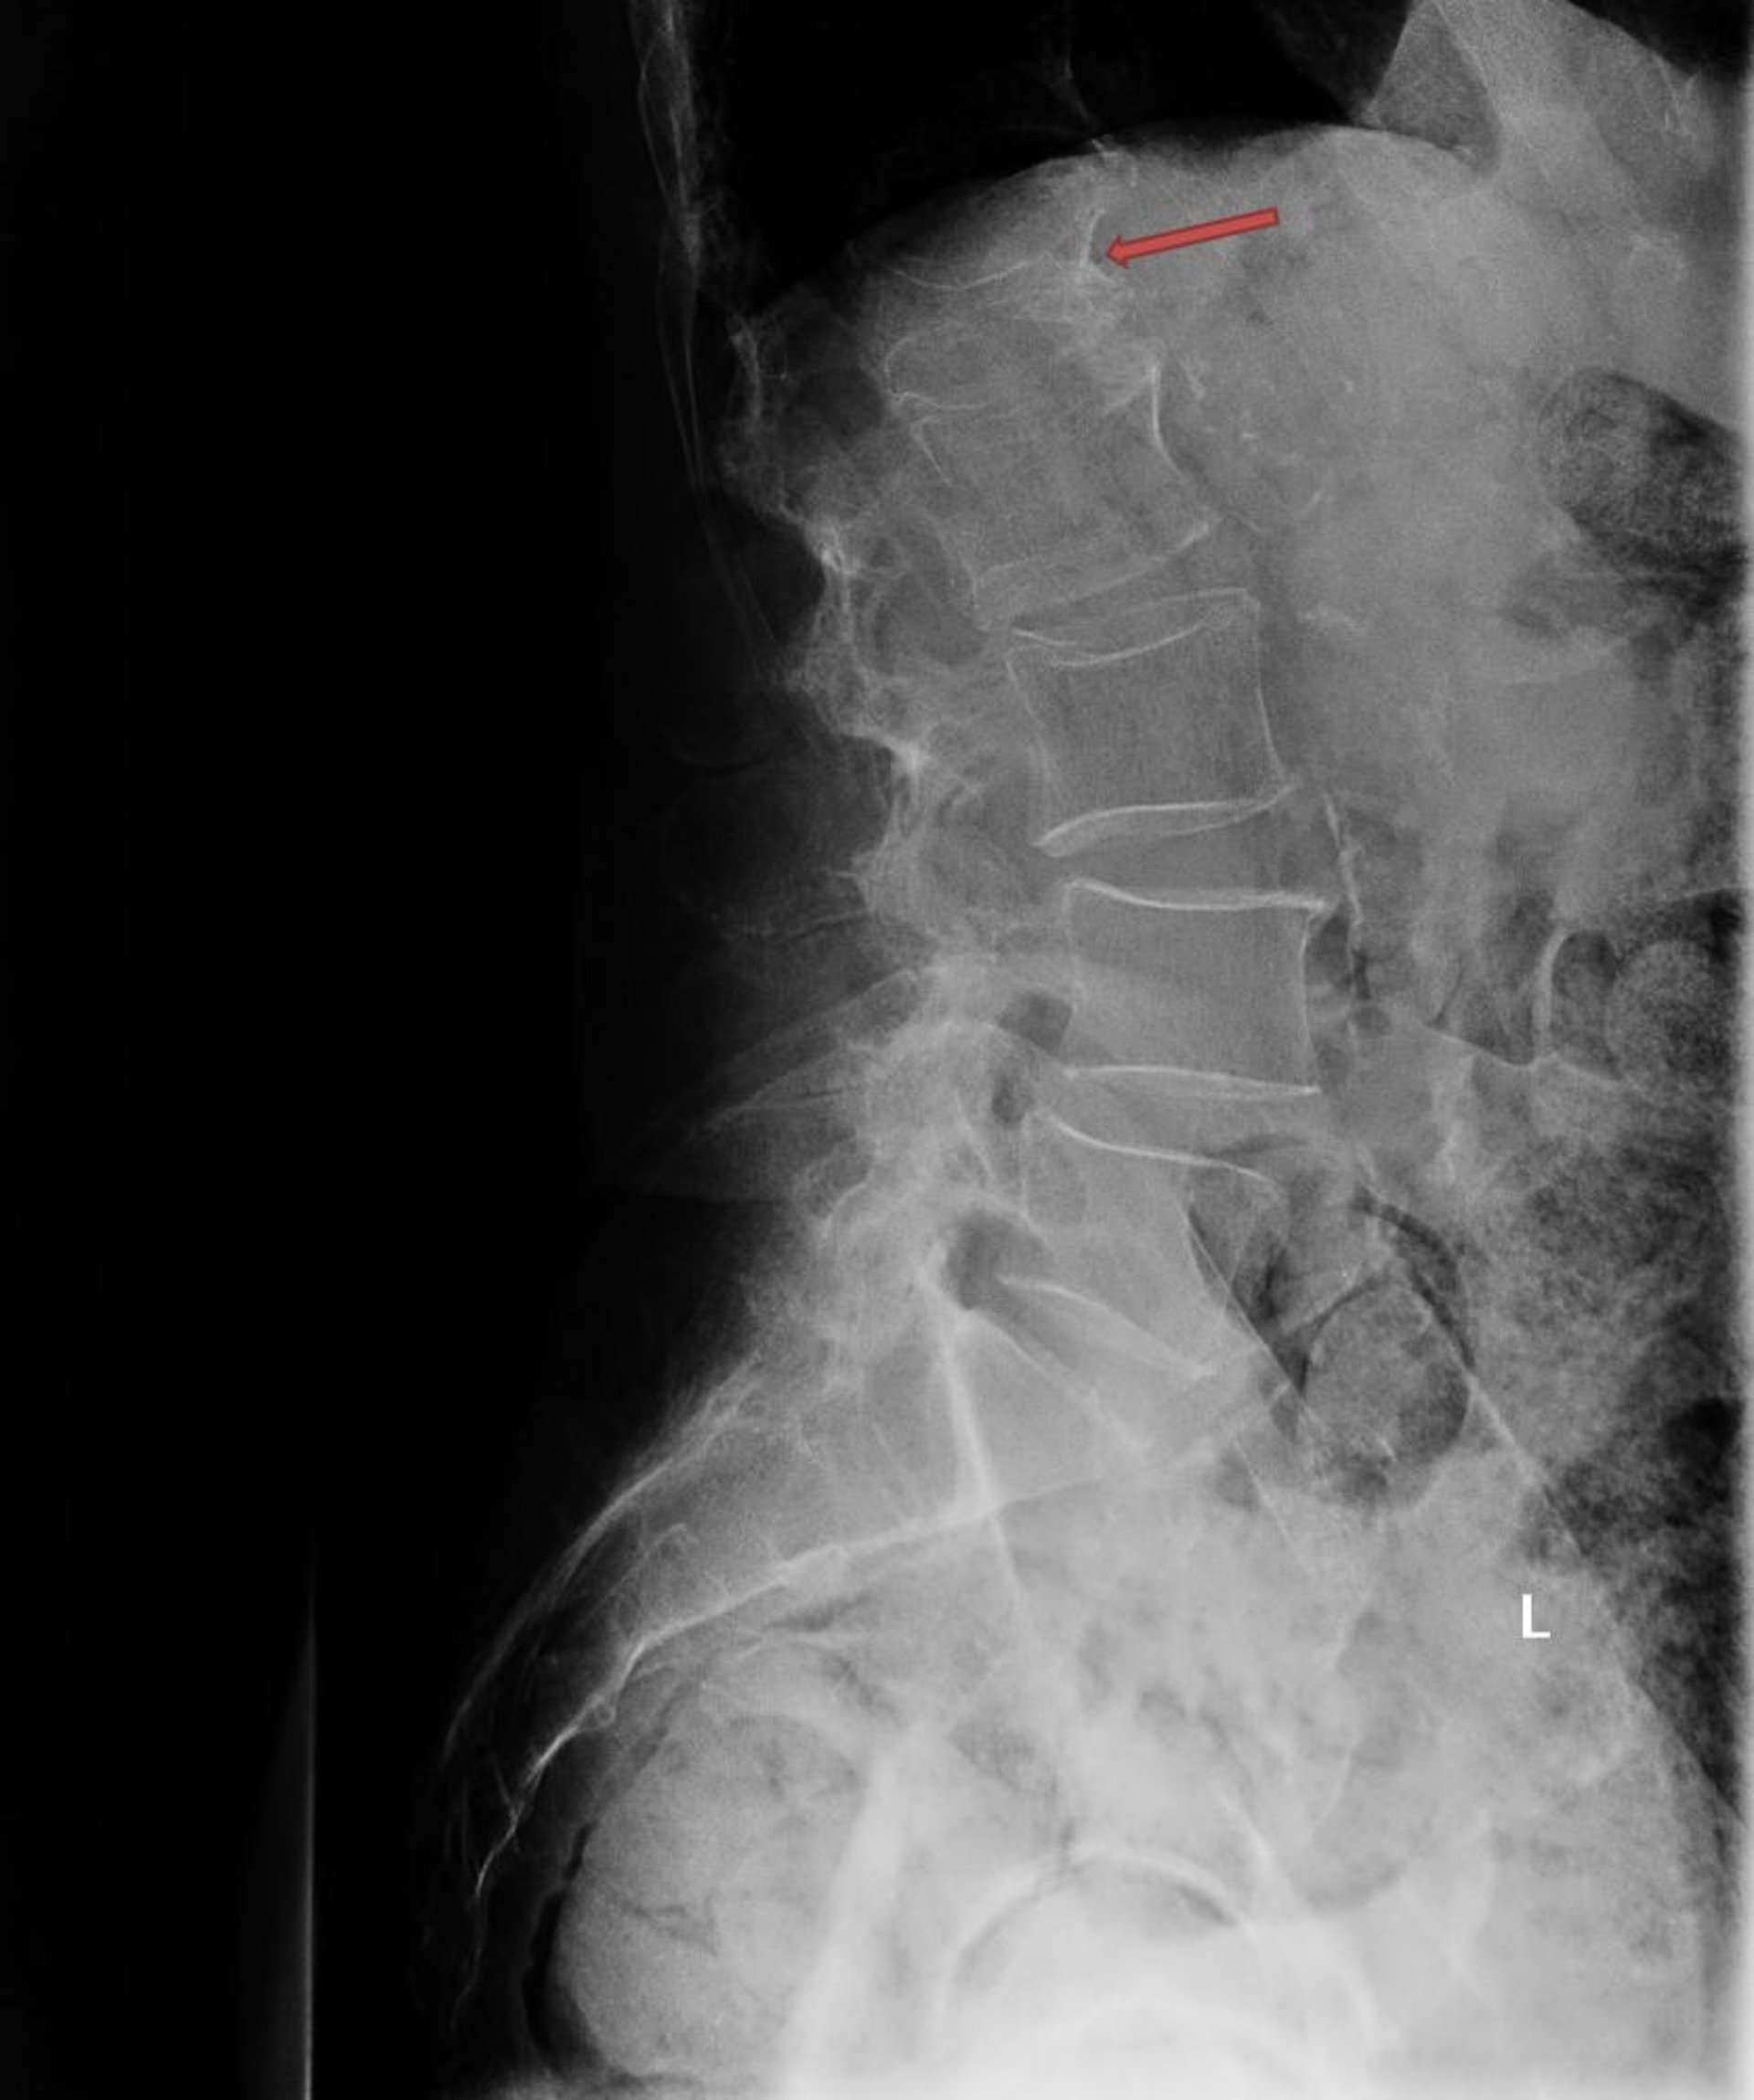

Frattura osteoporotica da compressione

Questa RX mostra una grave frattura da compressione osteoporotica della prima vertebra lombare (L1; freccia).

Photo courtesy of Marcy B. Bolster, MD.